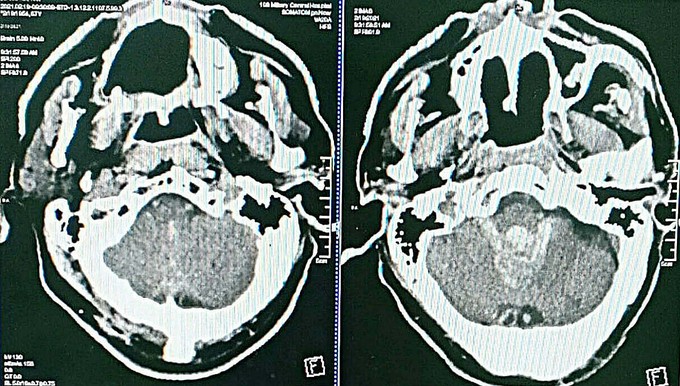

Đột quỵ máu chảy gây lụt não thất

Ông được chuyển tuyến đến Bệnh viện Trung ương Quân đội 108 trong tình trạng hôn mê sâu, liệt tứ chi do chảy máu não thất, giãn cấp tính hệ thống não thất, đe dọa tử vong.

Bác sĩ Nguyễn Thị Loan,Trung tâm Đột quỵ, Bệnh viện Trung ương Quân đội 108, ngày 13/3 cho biết trước đây những người bệnh chảy máu não thất lớn gây lụt hệ thống não thất như bệnh nhân này tỷ lệ tử vong là 100%. Lý do là máu chảy vào trong não thất đóng bánh lại thành khuôn không thể dẫn lưu ra ngoài.

Với kỹ thuật này, thuốc tiêu huyết khối được tiêm qua dẫn lưu vào não thất làm tan khối máu đông và theo dẫn lưu chảy ra ngoài. Kỹ thuật mới mở ra cơ hội cứu sống nhiều người bệnh chảy máu não thất nặng tại bệnh viện.